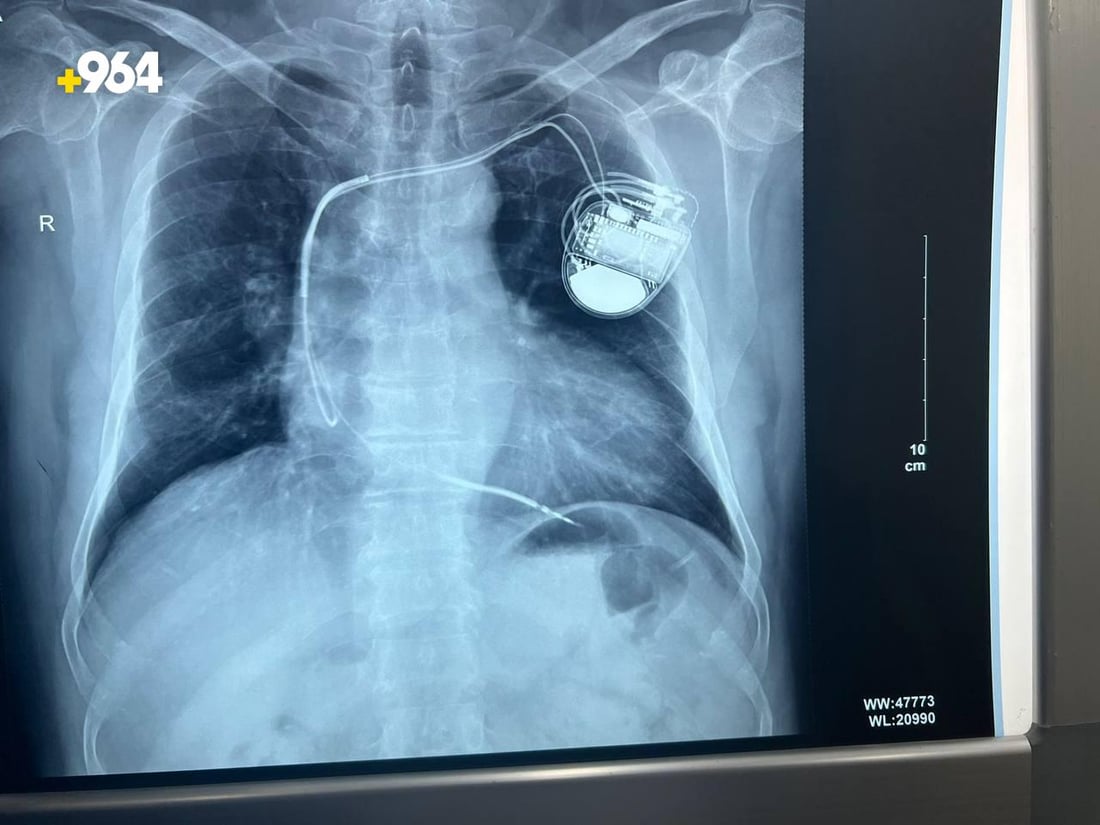

دهوك: 300 مريض يزرعون بطارية لتنظيم دقات القلب.. الضمان 10 سنوات (صور)

قال طبيب متخصص في دهوك، إن 300 مريضاً زرعوا هذا العام بطاريات خاصة بتنظيم ضربات القلب، في زيادة ملحوظة عن العام الماضي، مشيراً إلى أنها ستبقى تعمل في أجسادهم 10 سنوات بشكل متواصل.

بطاريات القلب أنواع؛ منها الخط، الأحادية، الثنائية، والثلاثية، وتستخدم جميعها لزيادة  عدد ضربات القلب، لأن انخفاضها لأقل من 40 في المئة من المعدل الطبيعي، يتسبب بضيق التنفس وفقدان الوعي، فتقوم البطارية بزيادة معدل الضربات أكثر من 60%.

معظم البطاريات تدوم 10 سنوات، لكن على المريض زيارة الطبيب كل 6 أشهر لإعادة برمجة البطارية.

عملية زرع البطارية تستغرق 40 دقيقة، ويبقى المريض تحت المراقبة لساعات، ثم يعود لمنزله في المساء.

حصل أكثر من 300 شخص في دهوك على بطاريات لقلوبهم حتى الآن، ومن المقرر أن يزداد العدد بنسبة 20 في المئة في نهاية عام 2023.